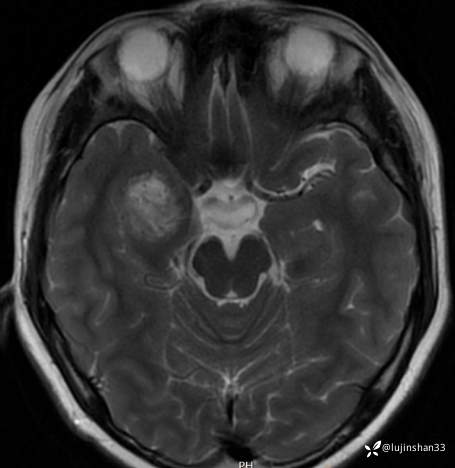

【主诉】:检查发现右侧颅中窝肿物3月

【现病史及既往史】:患者3月前头部磕碰后感疼痛,当时被老师送到XX市XX县人民医院,行CT检查提示颅内肿物,又继续到XX省第二人民医院行头颅核磁示:右侧颅中窝肿物,建议手术治疗,于7月23日入住我科拟行手术,但患儿极度不配合,办理出院回家调整,现完善心理建设,要求手术。

【临床诊断】:颅底占位

【治疗经过及结果】:显微镜下颅中窝入路右侧颅底病变切除术,术后恢复良好。